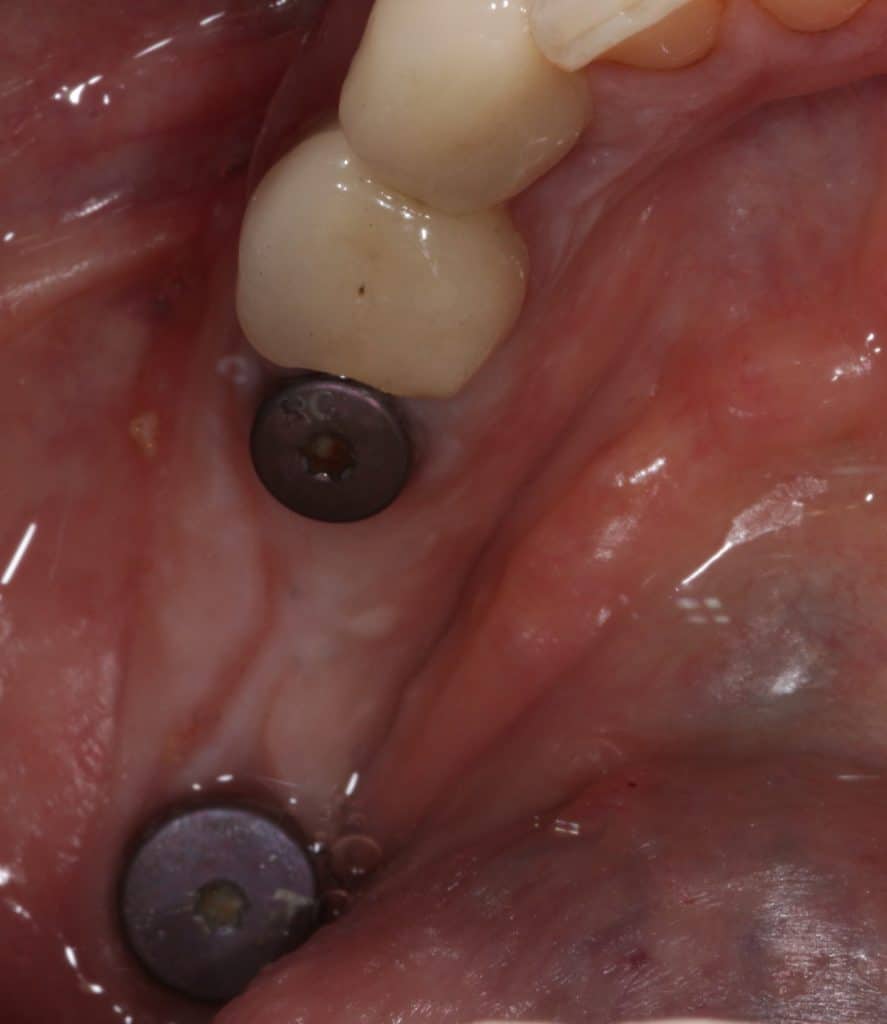

Tissue condition at the time of reopening

Implants re-opening